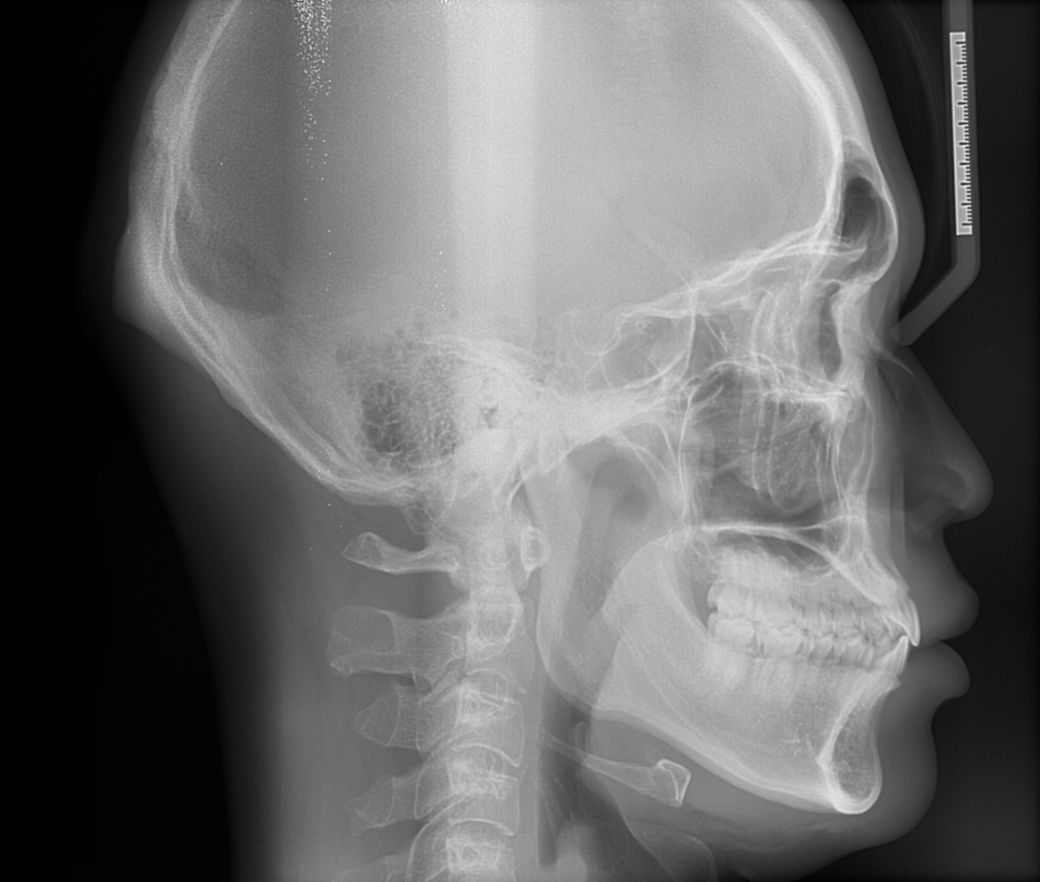

중안면부 꺼짐있는경우 양악을 하면 개선이 되나요?

중안면부 꺼짐있는 경우 미용적인 목적으로 양악수술을 하면 개선이 되나요?

보통은 이런경우 코수술을 하게되나요?

치아 교합은 정상인데 일자목이라서 그런건지모르겠지만 옆모습을 봤을때 입체적이지 않고 약간 1자 모습? \\모양 이여서 콤플렉스입니다.

양악 수술을 하여 현재 안모를 개선시킬 수 있어 보이지만 추천드리지는 않습니다. 현재 보이는 방사선 사진에서 3급 부정교합이기는 하나 안모상으로 크게 문제가 되는 정도는 아닙니다. 지금보다 훨씬 하악이 앞으로 나오거나 상악이 뒤로 위치할 경우에 심미적인 목적과 더불어 교합이상으로 양악을 추천하나 현재 수준에서는 양악을 잘 하지 않습니다.

현재 자료를 놓고 평가해보면, 하악골이 살짝 돌출된 정도로 보입니다. 그러나 그 정도가 심하지 않습니다.

한마디로 본인이 원하신다면 미용적인 목적으로 양악수술을 받는 경우가 될 수는 있겠으나, 무조건 수술을 해야하는 케이스는 절대 아닙니다.

약간 턱이 나오신것같지만 크게 문제는 없어보입니다. 기능상에 문제가 있다면 교정이나 수술을 통해서 해결해야되지만 기능상의 문제가 없으시다면 심미적인 부분이 클텐데 이건 작성자님의 선택사항입니다. 치료를 원하신다면 양악수술도 고려해보셔야될것같습니다